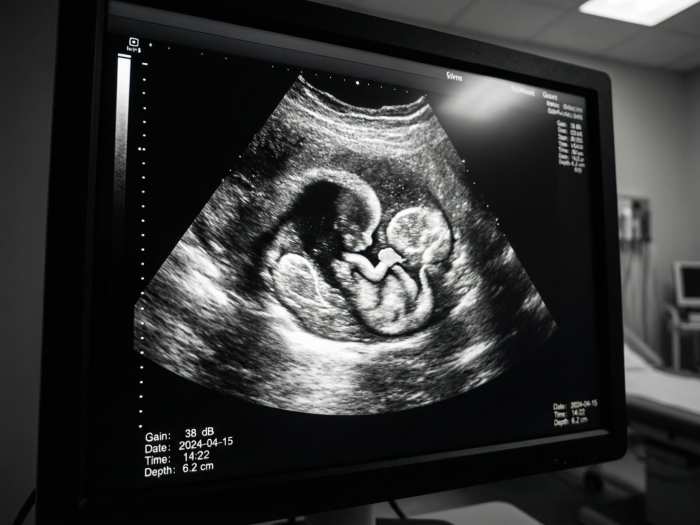

Lyme disease and pregnancy represent an underexplored global health issue with potentially far-reaching consequences. Worldwide, millions of people may be living with undiagnosed Borrelia infection acquired before birth, yet this pathway of transmission remains largely overlooked.

This article presents global projections of undiagnosed congenital Lyme disease, using mathematical models based on incidence, prevalence, and seroprevalence data. By combining birth statistics, transmission probabilities, and diagnostic gaps, the analysis sheds light on how intrauterine Borrelia transmission could affect populations across decades.

Understanding pregnancy-related Lyme disease risk is essential not only for clinicians, but also for public health planning. The findings suggest that the global burden of undiagnosed infection may be substantially higher than currently recognized, warranting renewed scientific and medical attention.